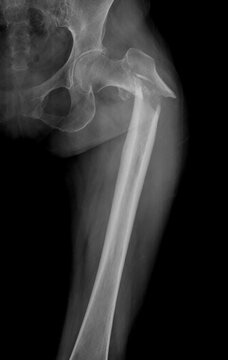

En el último episodio de Artro Esport Podcast, el Dr. Fraguas explica las innovaciones que previenen la fractura de fémur. Lo hace en este capítulo en formato entrevista. Asimismo, el especialista nos detalla en profundidad qué cambios comportan estas nuevas aplicaciones.